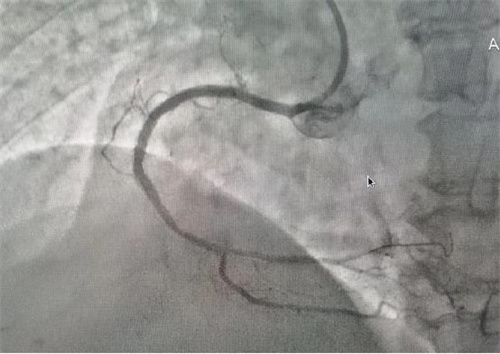

術(shù)中

據(jù)了解,此次順利完成經(jīng)皮冠狀動脈內(nèi)支架植入術(shù)的患者共有4位,其中一名68歲老年女性患者,因胸悶氣促6余年,活動后明顯加重入院治療。經(jīng)冠脈造影檢查,發(fā)現(xiàn)左前降支次全閉塞、右冠99%重度狹窄,三支血管重度病變,情況危急。經(jīng)病情評估后,與患者家屬溝通,決定立即對右冠實施冠狀動脈球囊擴張加支架植入術(shù)。在上級專家的指導下,心病科團隊成功擴張了狹窄血管、植入支架,手術(shù)順利,患者術(shù)后安返病房,為患者后續(xù)治療創(chuàng)造了有力條件。